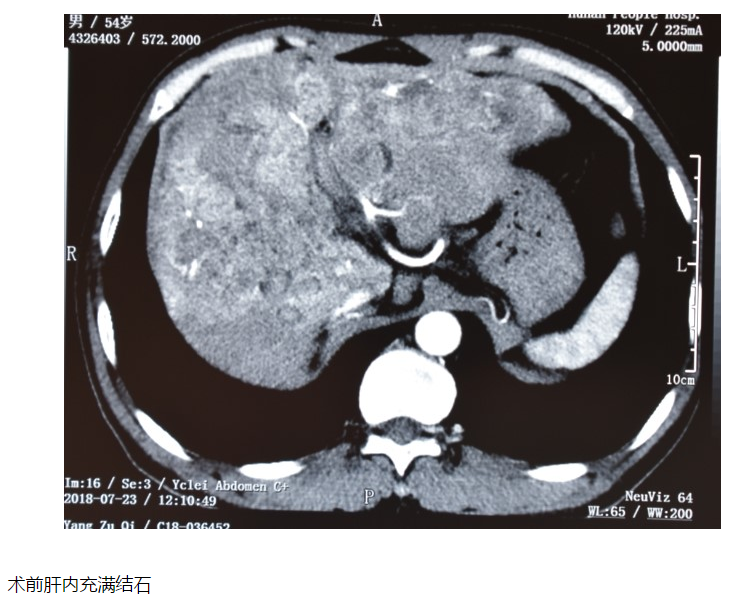

湖南54歲男子肝內(nèi)取出251克結(jié)石

湖南54歲男子肝內(nèi)取出251克結(jié)石 罪魁禍?zhǔn)拙故莾簳r(shí)未驅(qū)干凈的蛔蟲 湖南省人民醫(yī)院 08-06 18:09 近日,湖南常寧男子齊忠良的肝內(nèi)取出半斤結(jié)石,而罪魁禍?zhǔn)拙故腔紫x!據(jù)悉,54歲的齊忠良曾在七八歲時(shí)就患過膽道蛔蟲,不僅嘔出死的蛔蟲,吃了驅(qū)蟲藥后還拉出大量活的蛔蟲。 由于膽結(jié)石,齊忠良在8年前做了開腹手術(shù)切除膽囊;6年前又做了腹腔鏡膽道探查手術(shù)。2018年7月初,齊忠良出現(xiàn)發(fā)熱和右上腹、肩背部疼痛,輸液后有所緩解,半個(gè)月后復(fù)發(fā),在當(dāng)?shù)蒯t(yī)院做B超發(fā)現(xiàn)“肝內(nèi)膽管結(jié)石”。由于病情較重,于7月19日轉(zhuǎn)往長沙,住進(jìn)湖南省人民醫(yī)院膽道外二科病房。 入院完善相關(guān)檢查后,齊忠良被診斷為“肝膽管結(jié)石、膽道梗阻、膽源性肝硬化、右后葉膽管狹窄”。 從CT片上可以看到,他的整個(gè)肝臟布滿結(jié)石,最大的石頭直徑有50mm;同時(shí)左肝肥大、右肝萎縮,肝內(nèi)膽管極度擴(kuò)張——原本直徑只有5~6mm的膽管,最粗直徑竟然達(dá)到30mm。不僅如此,齊忠良的膽管先天變異——右肝管缺如,右后葉膽管開口在左肝管上。如果不及時(shí)手術(shù),病情進(jìn)一步發(fā)展,將導(dǎo)致膽道休克、肝昏迷、肝衰竭,危及生命。 在反復(fù)討論病情、制訂周密的手術(shù)方案后,7月24日,膽道外二科陳晨副主任醫(yī)師為患者施行手術(shù)。由于患者曾經(jīng)做過手術(shù),腹腔內(nèi)粘連嚴(yán)重;經(jīng)歷過膽囊次全切手術(shù),導(dǎo)致膽囊分離困難;右肝管狹窄,常規(guī)途徑(肝圓韌帶途徑、膽囊床途徑)無法進(jìn)入肝臟。 在此情況下,手術(shù)團(tuán)隊(duì)只得另辟蹊徑,采用膽管高位切開、肝門膽管成形、盆式內(nèi)引流術(shù),結(jié)合硬質(zhì)膽道內(nèi)鏡鈥激光碎石,解除肝門部膽管的狹窄,重建新的膽管流出通道,充分取出結(jié)石。經(jīng)過近10個(gè)小時(shí)的手術(shù),最終取出251g結(jié)石,創(chuàng)下近年醫(yī)院肝膽管結(jié)石手術(shù)重量之最。 “過去,我國農(nóng)村生產(chǎn)、生活條件較差,膽道蛔蟲發(fā)病率很高”,陳晨教授介紹,導(dǎo)致齊忠良肝膽管結(jié)石的罪魁禍?zhǔn)拙褪恰澳懙阑紫x病”。此病在上世紀(jì)六七十年代多發(fā),與當(dāng)時(shí)的農(nóng)村生活條件和衛(wèi)生習(xí)慣較差有著密不可分的關(guān)系,因此被稱為“窮病”。 蛔蟲成蟲通常寄生于人體的小腸中下段,因其喜歡昏暗、偏堿性的環(huán)境,尤其喜歡鉆孔,所以在人體內(nèi)游走。尤其在受到驅(qū)蟲藥或其他方式的激惹后,蛔蟲會(huì)極力上鉆,進(jìn)入膽總管。時(shí)間久了,經(jīng)過醫(yī)學(xué)治療,蛔蟲被殺死,但蛔蟲尸體的碎片、角皮、蟲卵等逐漸堆積,最終在肝膽管內(nèi)形成結(jié)石。 陳晨教授提醒,不明原因的上腹疼痛要及時(shí)就醫(yī);在兒童期進(jìn)行驅(qū)蟲時(shí),應(yīng)遵循醫(yī)囑用藥,因?yàn)橛行┧幬镌隍?qū)蟲時(shí),可能會(huì)在未殺死蛔蟲的情況下激惹蛔蟲,致使它們上鉆游離,進(jìn)入膽道,從而引發(fā)其他疾病。 陳晨副主任醫(yī)師